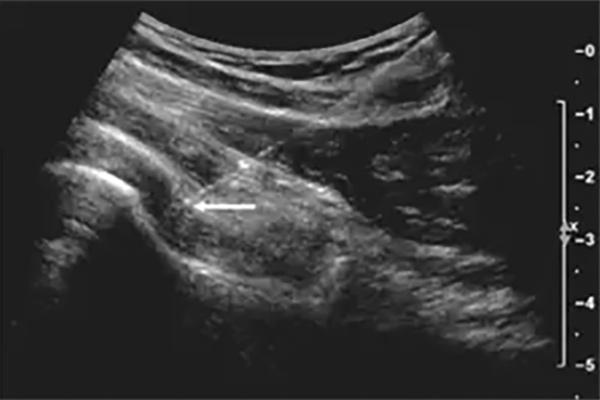

At the American Hip Institute, our providers are specially trained to perform ultrasound-guided injections with accuracy and care. These procedures are done conveniently in the office at the time of your visit. Ultrasound guidance allows us to clearly visualize the hip structures in real time, ensuring that the injection is placed precisely where it is needed. This technique increases the safety and effectiveness of the treatment while minimizing discomfort.

Ultrasound-guided injections may be used for both diagnostic and therapeutic purposes. One common type is the diagnostic injection, which involves injecting a local anesthetic into the joint. This helps us determine whether your pain is coming from within the joint itself. If the injection provides relief, even temporarily, it confirms that the source of the pain is intra-articular (inside the joint). It’s important to understand that this type of injection is not intended to treat the condition but rather to help us identify the cause of your symptoms.